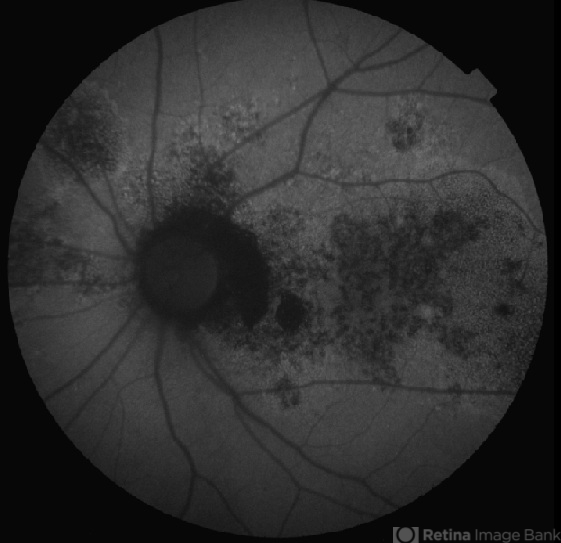

- multifocal central serous chorioretinopathy (CSCR), autofluorescence imaging

- A 47-year-old male presented with left eye diminision of vision since 2 months. Left eye fundus autofluorescence image shows multiple hypofluorescent areas with numerous discrete small hyperfluroscent dots suggestive of inactive chronic multifocal central serous chorio-retinopathy.